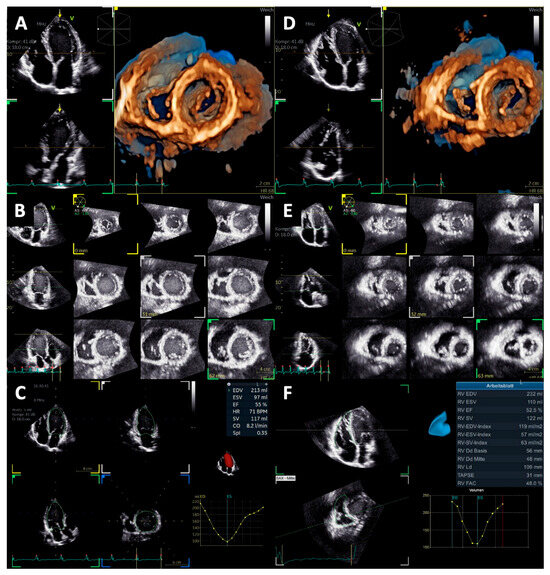

2.4. Left Heart Morphology and Function

2.5. Right Heart Morphology and Function